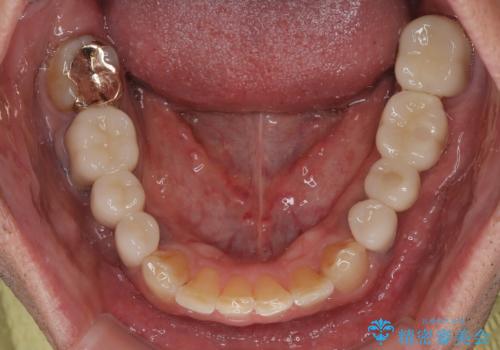

銀歯やむし歯治療されている歯を抜歯する治療計画としたため、やや時間はかかりましたが、治療後の仕上がりには大変満足していただけました。